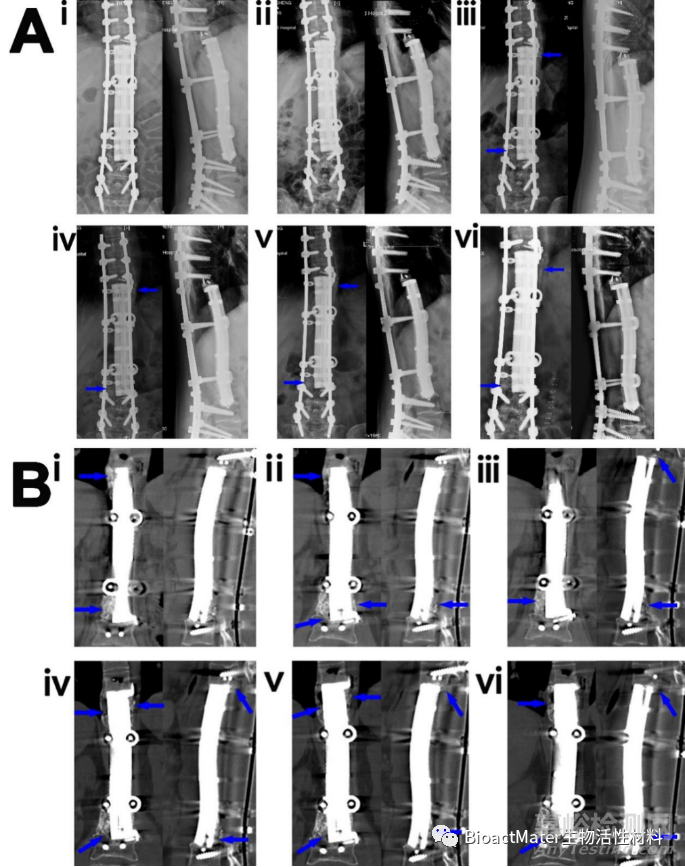

圖4.3D打印多孔Ti6Al4V內(nèi)植物重建脊柱骨缺損(病例1)。(A) (i-vi)術(shù)后1個(gè)月(i)、3個(gè)月(ii)、7(個(gè)月iii)、12個(gè)月(iv)、24個(gè)月(v)和32(vi)個(gè)月的“內(nèi)植物-骨”X線圖像。藍(lán)色箭頭表示內(nèi)植物與骨界面或內(nèi)植物外表面新生骨。(B)術(shù)后3個(gè)月(i)、7個(gè)月(ii)、12個(gè)月(iii)、28個(gè)月(ⅳ)、32個(gè)月(v)和36個(gè)月(vi)的CT圖像。藍(lán)色箭頭表示種植體-骨界面或種植體外表面新形成的骨。